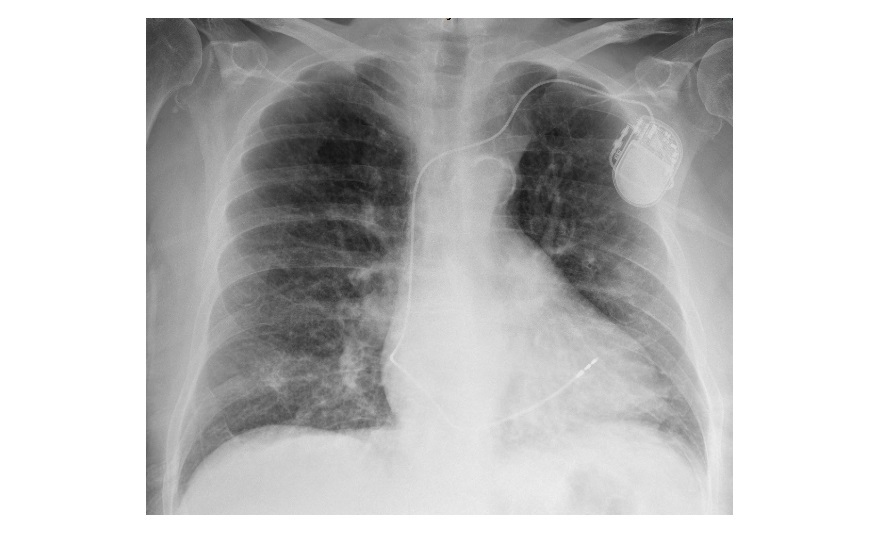

Heart block investigations CXR?

cardiac enlargement, pulmonary oedema

Chronic heart block management?

permanent pacemaker in complete heart block, advanced mobitz type 1 and symptomatic mobitz type 2